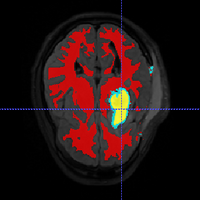

• Segment longitudinal brain MR images with TBI using personalized atlas construction.

• We got two new subjects from UCLA DBP. We processed the data and tested the current algorithm.

• Bo Wang, Marcel Prastawa, Andrei Irimia, Micah C. Chambers, Paul M. Vespa, John D. van Horn, Guido Gerig, A Patient-Specific Segmentation Framework for Longitudinal MR Images of Traumatic Brain Injury, SPIE Medical Imaging 2012.